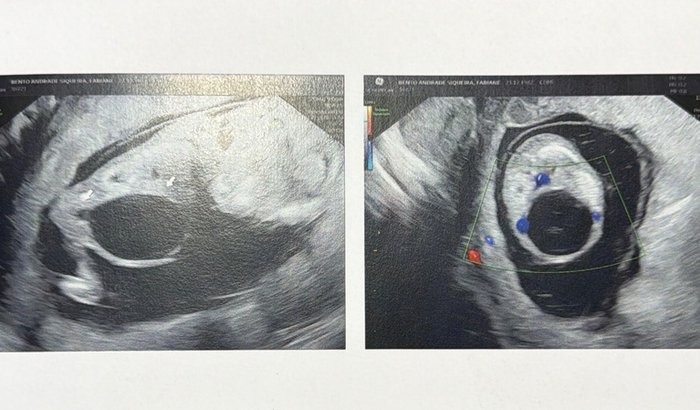

Nós somos Fabiane e Max, somos pais do João Gabriel, que ainda está em meu ventre. Estou com 13 semanas + 5 dias de gestação. No dia 02/04 foi detectado através de uma ultrason que nosso bebê está com uma má formação na Válvula da Uretra Posterior (VUP) o que impede dele fazer xixi. Infelizmente o custo da cirurgia intra uterina é muito alta e não temos condições de arcar. Essa cirurgia só é feita em São Paulo por profissionais de Medicina Fetal. Tenho até dia 16 de abril para estar em SP para fazer o rastreio dessa condição e confirmar a cirurgia. O tempo é nosso aliado ou nosso maior inimigo. Pois se a obstrução continuar nosso bebê poderá não chegar ao final da gestação, pois a falência renal é a principal consequência dessa condição. Por isso, queremos pedir seu apoio para salvar a vida do nosso filho.